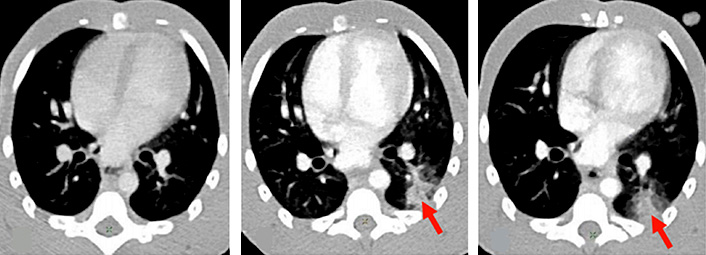

Les essais précliniques démarrent en parallèle des essais cliniques : paradoxalement, malgré le contexte de pandémie, les patients susceptibles d'être inclus dans des essais cliniques ne sont pas assez nombreux pour espérer obtenir des résultats suffisamment rapidement. Il faut contrôler tous les paramètres pour interpréter les résultats sans ambiguïté. Les équipes d'IDMIT étudient en détails les effets de la maladie : symptômes, lésions, dissémination du virus dans l'organisme, détection et dosage du virus par test PCR dans les différents tissus, évolution de la maladie, mécanismes immunitaires, modes de contamination, de transmission, … Certaines de ces données ne sont pas accessibles chez l'humain. Les échanges entre IDMIT et les cliniciens sont nombreux pour orienter au mieux les essais cliniques et les traitements. Les informations sont transmises à l'OMS, l'ANSM, REACTing et le Conseil Scientifique pour les aider dans leurs prises de décisions.